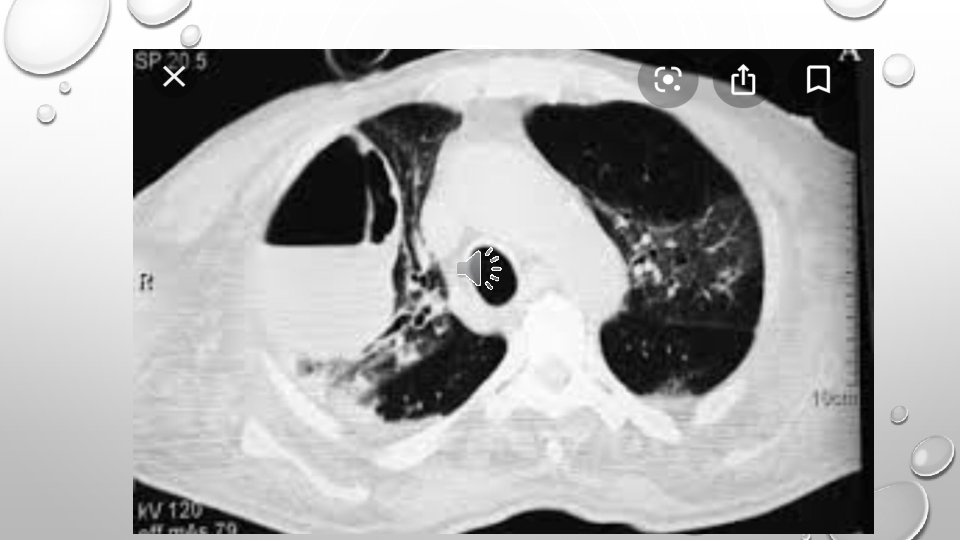

• LUNG ABSCESS REPRESENTS NECROSIS AND CAVITATION OF THE LUNG FOLLOWING MICROBIAL INFECTION • LUNG ABSCESS CAN BE SINGLE OR MULTIPLE

• LOCALIZATION OF INFECTION IN PRIMARY LUNG AB. IS IN POSTERIOR UPPER LOBE AND SUPERIOR LOWER LOBES • RIGHT LUNG IS AFFECTED MORE COMMONLY • MICROBIOLOGY IS POLYMICROBIAL • A PUTRID LUNG AB. REFERS TO CASES WITH FOUL SMELLING BREATH , SPUTUM, OR EMPYEMA

DIAGNOSIS • IMAGING • NEEDLE ASPIRATION

PROGNOSIS • P. LUNG AB. ≤ 2% • SEC. LUNG AB. =75% • POOR PROGNOSTIC FACTORS: • AGE≥ 60 • THE PRESENCE OF AEROBIC BACTERIA • SEPSIS AT PRESENTATION • SYMPTOM DURATION ≥ 8 WEEKS • ABSCESS SIZE≥ 6 CM